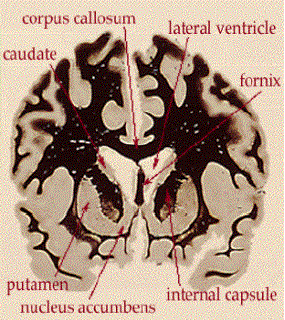

Lo striato ventrale e la

memoria

Posizione dello striato

ventrale

Rappresentazione schematica

degli input e output del nucleo accumbens

Laccumbens è

coinvolto nel processamento dellinformazione spaziale, anche in

assenza di rinforzi.

I recettori AMPA e NMDA (bloccati

con diversi antagonisti) modulano differenti aspetti del

processamento dellinformazione spaziale.

Lo striato ventrale è

uninterfaccia tra le funzioni cognitive e la loro espressione

comportamentale e gioca un ruolo critico nelle memorie e

comportamenti ricorrenti.